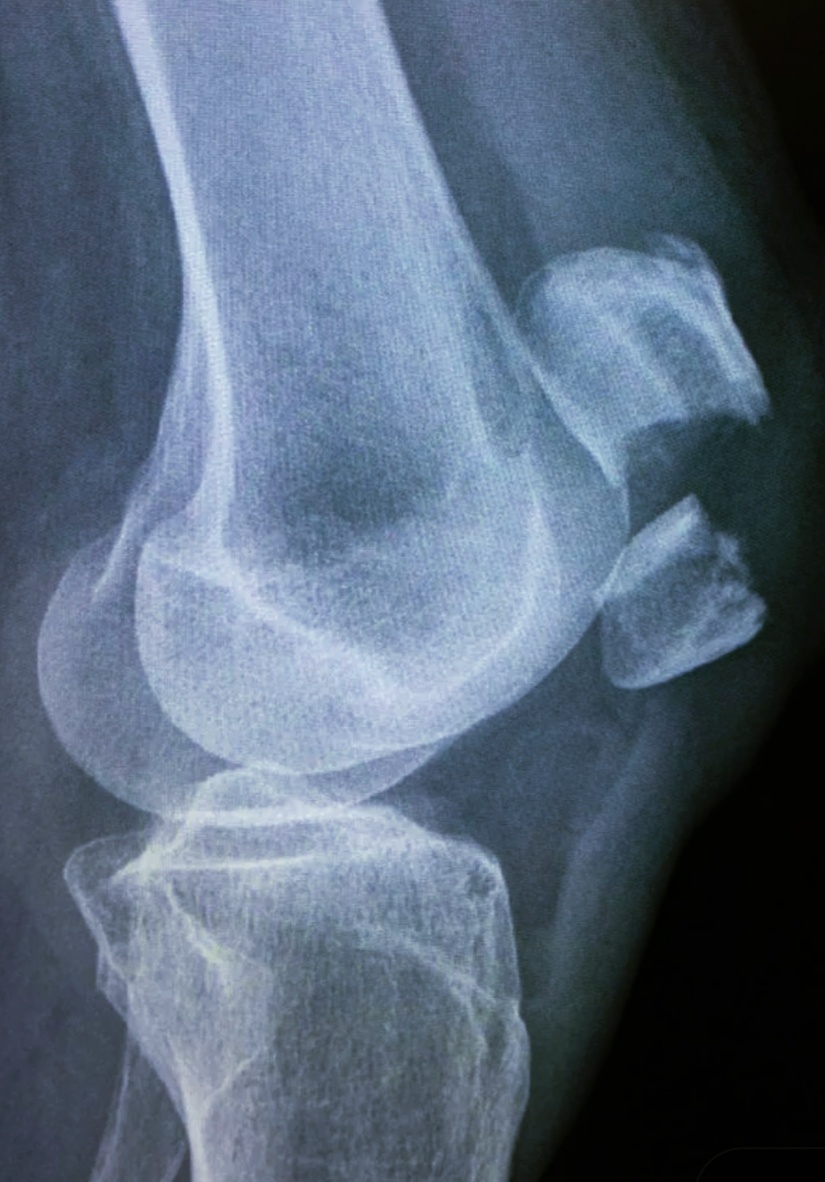

Как бы не так, уже стоит каталка, с мужчиной. Автодорожка. Мужчина, 57 лет , в сознании. Назначили все по стандарту, после осмотра:голова, легкие, кости таза и оба колена.

С головой быстро с Борисом управились , с легкими тоже, а под ягодицы стали кассету подкладывать, пациент закричал. Ни на одну ногу опереться не может.

Справились, на наш взгляд, таз целый.

Коленные суставы снимали , подсунув кассету под рентгеноконтрастный матрас. Сильно пациенту больно было.

У нас так принято в приемнике делать снимки с более захватываемой площадью , чем написано в направлении.

То есть, после травмы , особенно автодорожной, чисто коленный сустав не снимаем, а обязательно с захватом и бедренной кости и обеих берцовых.

Да уж, правый надколенник сломан и левая бедренная кость, нижняя треть.

Надколенник соберут путем секреляжа, что это такое я описывала в телеграм, а бедренную кость, наверное растягивать будут, Илизарова поставят, потом глянем, как наш пациент лечится.